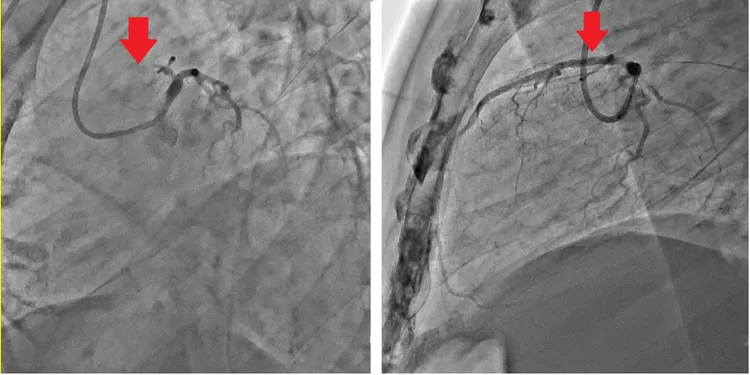

患者血管嚴重狹窄(左),打通後恢復血流(右)。院方提供

劉昱成醫師表示,血糖值和膽固醇值高,長期下來極易導致心血管病變,此患者心導管影像顯示血管內層不平滑凹凹凸凸,寬窄不一,最狹窄處連顯影液幾乎都流不過去,代表此區血液供應極為不穩定,因為血液流量不足,無法充足輸送足夠的氧氣和養分給該區心肌細胞,故會產生心肌梗塞,嚴重時會危及生命。

所幸該患者在造勢活動結束後,由友人護送到急診室,經抽血檢查和心電圖檢查後由值班心臟內科接手,經心導管團隊檢查發現在心臟血管左前降支有處最嚴重狹窄的病灶,經心導管的血管內氣球擴張和血管支架置放後,血液立刻暢通,患者不適的症狀也迅速改善,後續住院觀察數天後狀況穩定,現已康復出院。